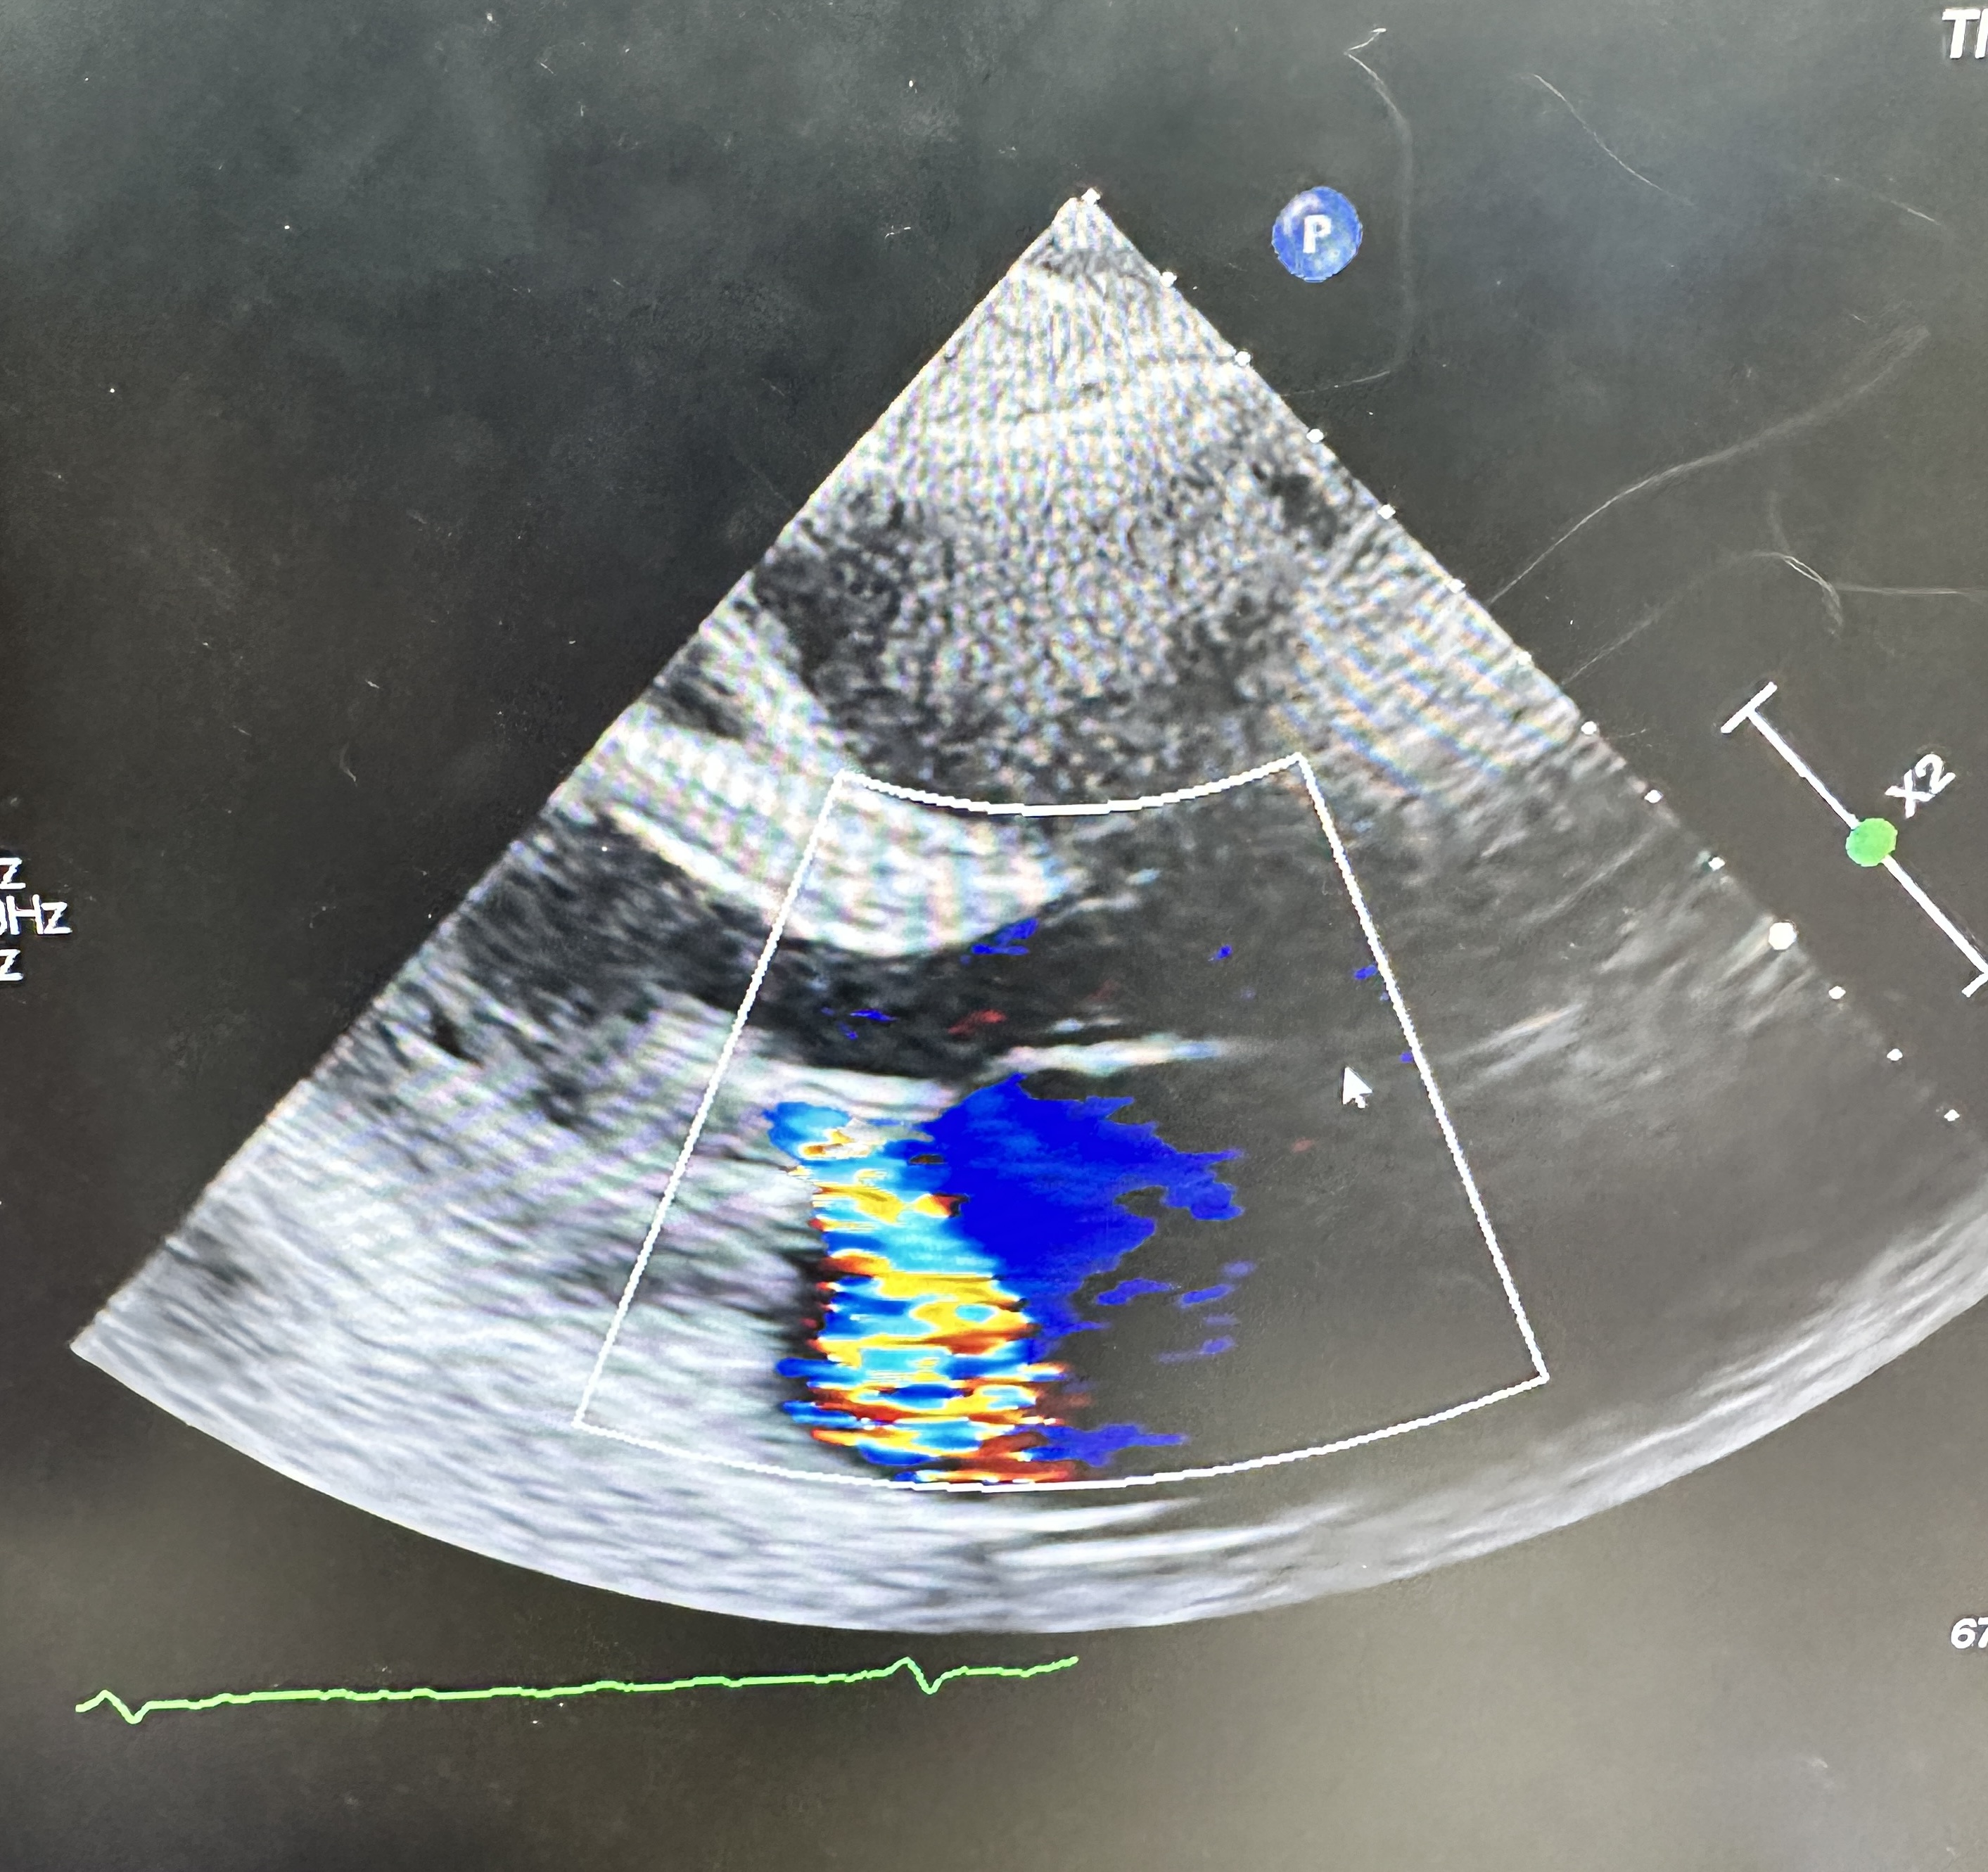

ECG: AF without acute ischemic change.CXR:CardiomegalyEchocardiogram: Severe primary (degenerative) mitral regurgitation due to mitral valve prolapses with flail P2 segment (Carpentier Type II), by integrative criteria (EROA ¡Ã0.4 cm©÷,regurgitant volume ¡Ã60 mL, vena contracta ¡Ã0.7 cm, systolic PV flow reversal,dense triangular CW jet). Baseline ECG: sinus rhythm without acuteischemic change.